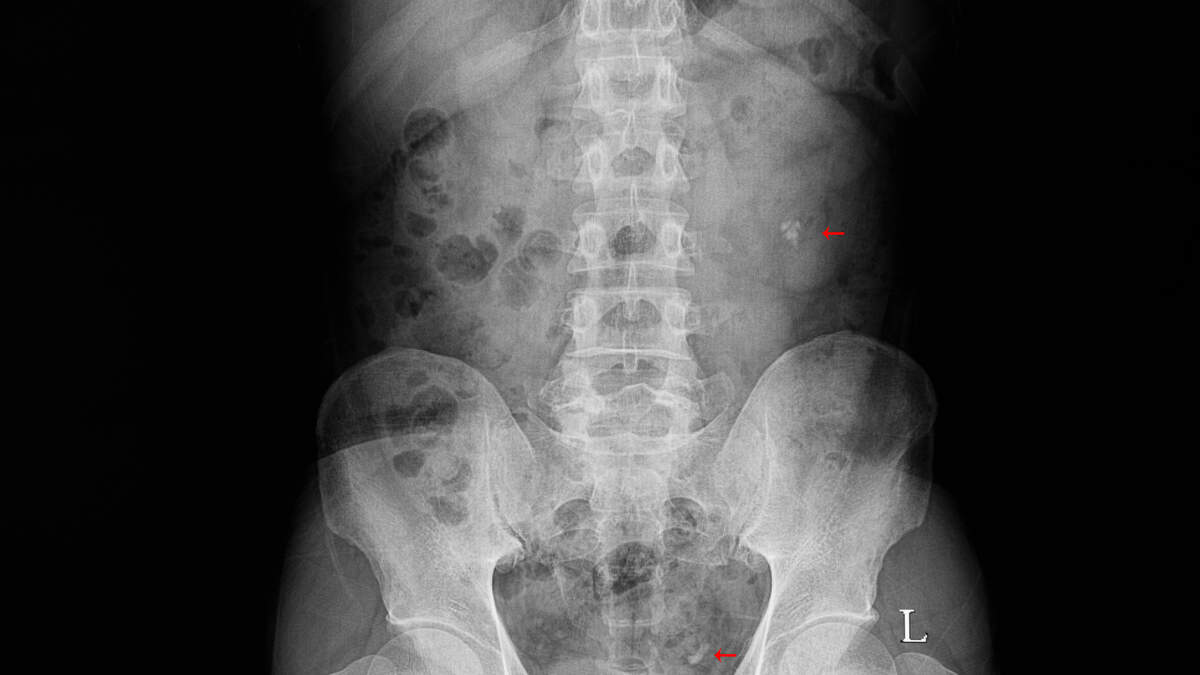

Doctors in Russia successfully removed a large glass jar from a man's bowel after a risky surgery. The man had inserted the pint-sized glass during a sexual act, which could have led to severe bleeding or fatal organ damage if the jar shattered inside him.

X-ray images revealed the jar had moved high into his bowel. Despite the dangers, doctors managed to remove it in full, along with a condom and lubricant, without breaking the glass. Hospital spokesperson Alexey Nikonov emphasized, "Doctors are not the morality police," urging patients not to hesitate to seek medical help in such situations.